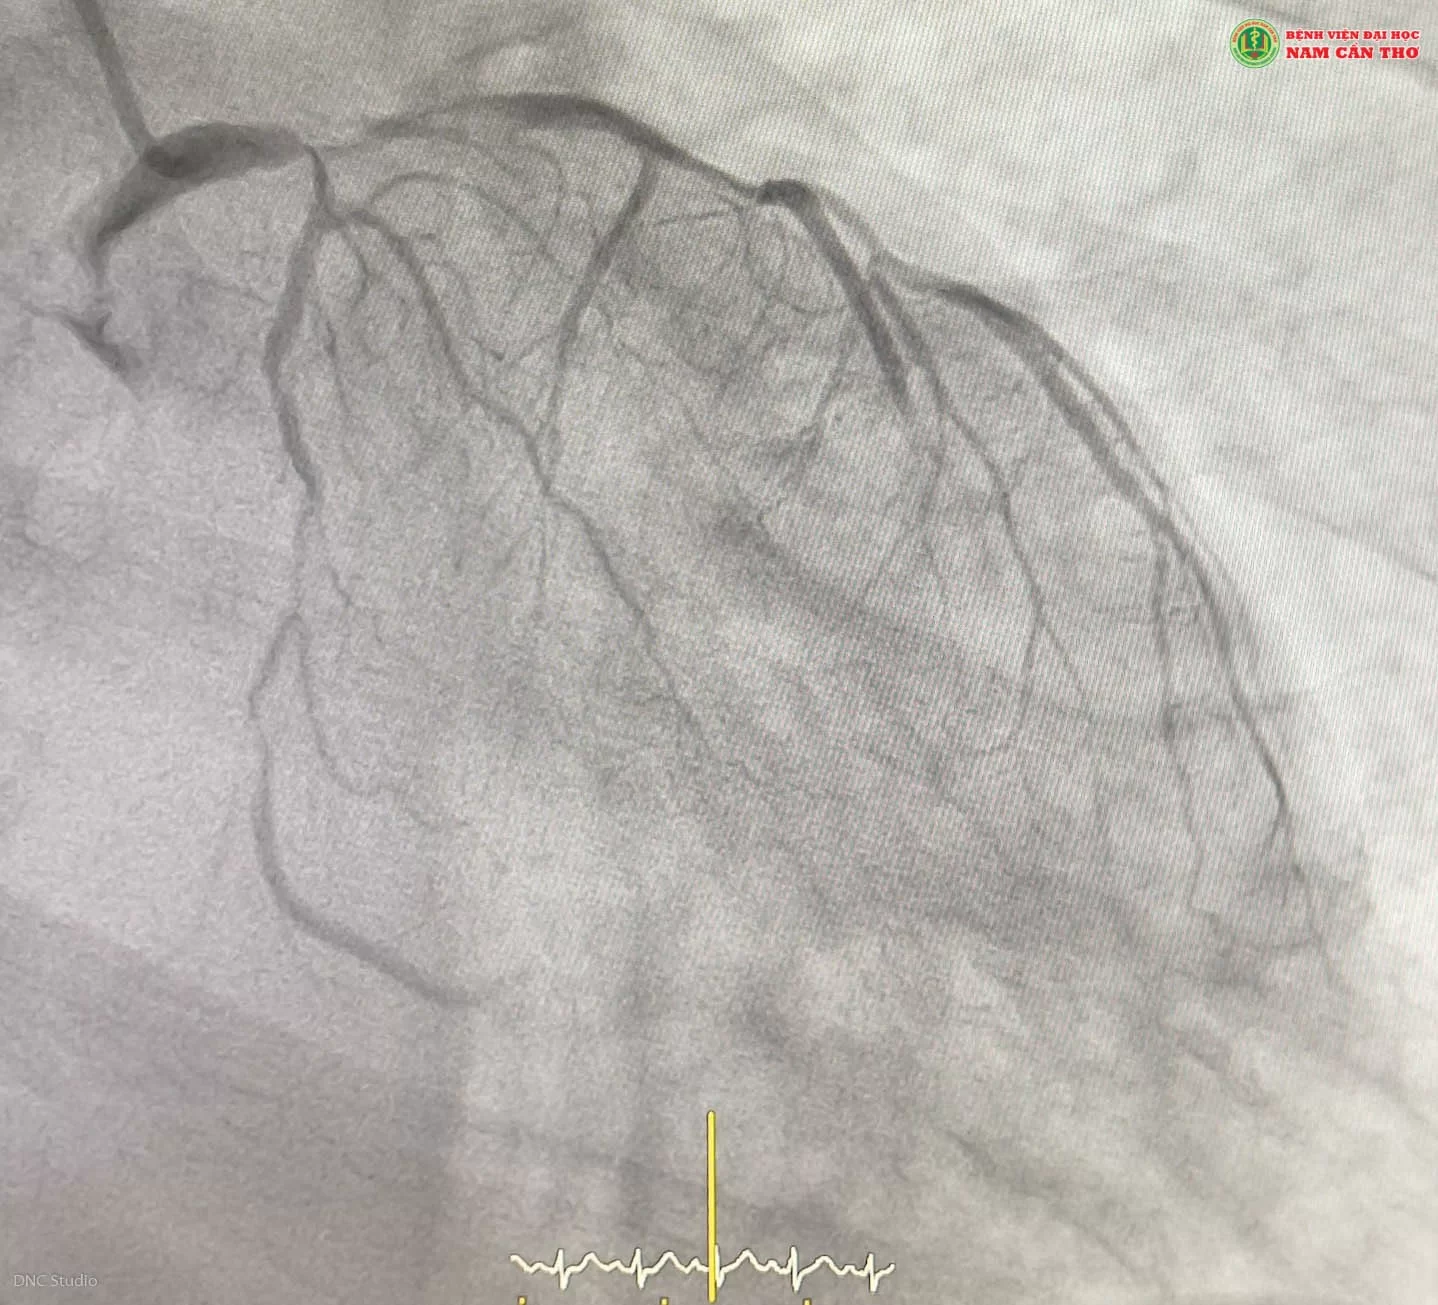

Kết quả chụp DSA trước khi can thiệp của bệnh nhân T.V.P (Ảnh DNC Studio)

Bệnh nhân được các bác sĩ tại Khoa Tim mạch và Can thiệp tim mạch đưa đến phòng can thiệp DSA để chụp và can thiệp động mạch vành cấp cứu. Kết quả động mạch vành hẹp nặng ngay gốc LM và hẹp nặng cả 3 nhánh động mạch vành. Trong đó 2 nhánh lớn bên trái (LAD, LCX hẹp dài lan tỏa và chậm dòng). Nguy cơ tim có thể ngưng đập tại chỗ.